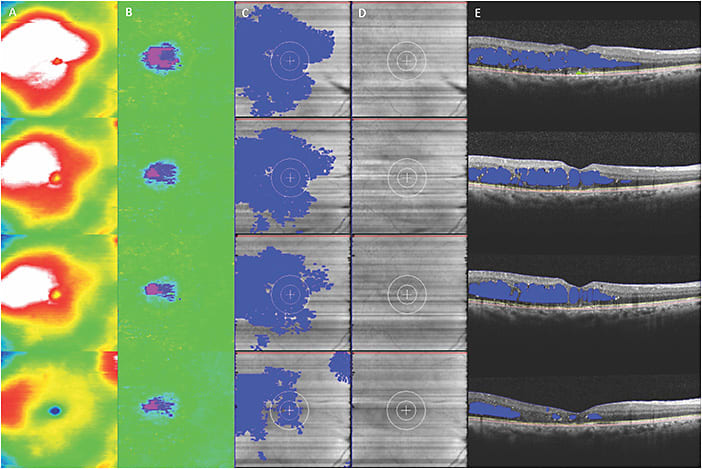

In addition to DR screening, AI systems have the potential to identify new features that may not be detectable by the human eye. For instance, deep learning algorithms may be capable of incorporating existing complex biomarkers like ultra-widefield fluorescein angiography (UWFA) biomarkers (non-perfusion area, ischemic index, leakage and microaneurysm counts)22,23 (Figure 1) as well as optical coherence tomography biomarkers (central subfield thickness, disorganization of retinal inner layers, hyperreflective foci, ellipsoid zone integrity, retinal fluid index and retinal fluid volatility)24-29 (Figure 2). These biomarkers have shown a correlation with DR severity, and many of these parameters, such as quantitative UWFA parameters, have been strongly associated with DR severity and risk of vision loss.23 Utilizing these systems, both panretinal and zonal vascular features can be extracted. The findings indicated that retinal vasculature features measured with AI systems demonstrated a correlation with DR severity, as well as visual and subvisual vascular biomarkers.30